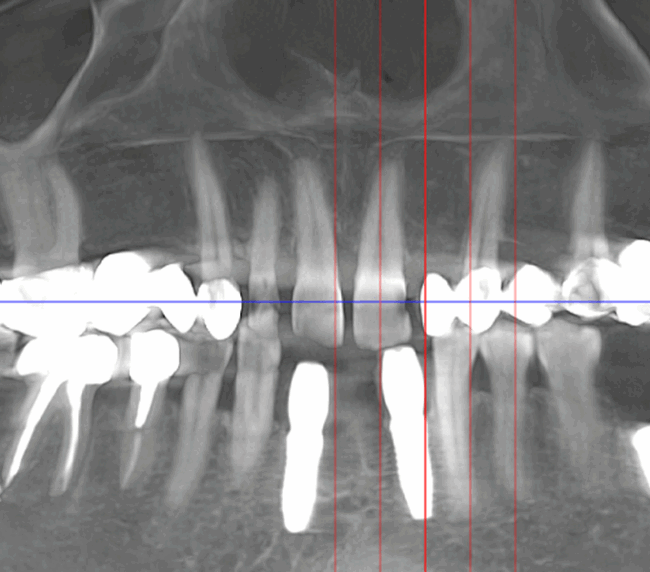

- Consultație, radiografie și plan de tratament personalizat

- Șlefuirea dinților de susținere sau inserarea implanturilor

- Ai deja implanturi inserate și ai nevoie de restaurare protetică